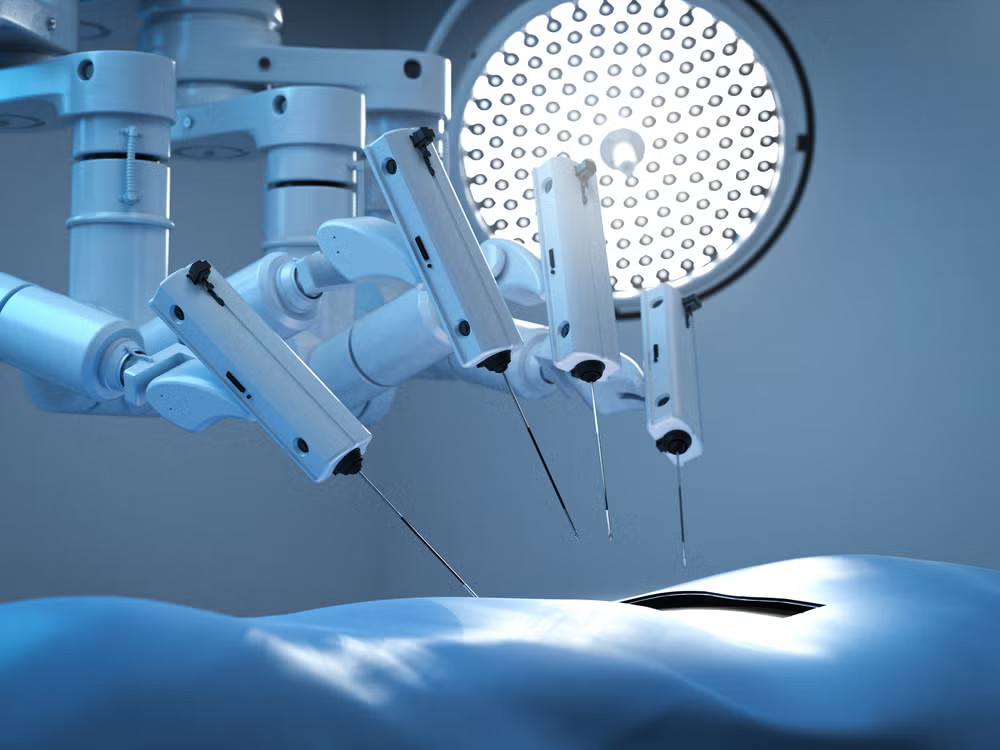

Introduction Surgery is evolving, and technology is transforming how patients experience care. Max Super Specialist Hospital is proud to announce...

Surgery can be a source of anxiety for many patients due to concerns about pain, recovery time, and outcomes. Over...